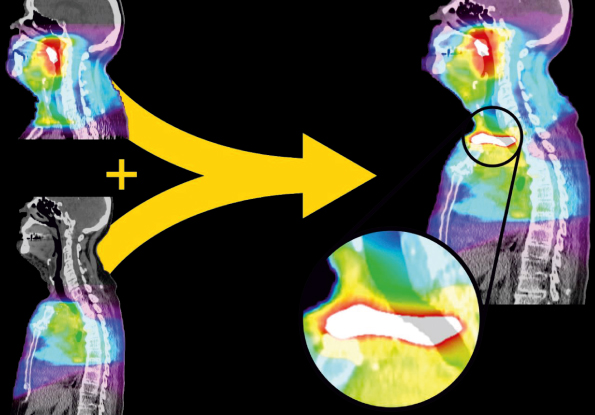

Doz Akümülasyonu

Herhangi bir sayıda planlar, deforme edilebilir şekilde akümüle edilebilir.

MIM Maestro ve VoxAlign Deformation Engine aracını birlikte kullanarak çoklu dozları kısa sürede deformasyon yapabilirsiniz ve bunları yeni tedavi planlama CT’sine aktararak hastaya verilecek toplam dozu daha iyi görselleştirebilirsiniz.

MIM’in deformasyon özellikleri sayesinde, farklı aylarda yapılmış tarama görüntüleri, deforme edilerek hizalanabilir, böylece doz dağılımı doğru şekilde gösterilir ve tedavi planlama sürecine duyduğunuz güven artar.